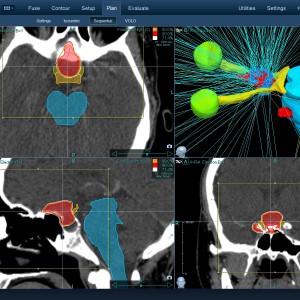

Στις παρακάτω φωτογραφίες θα δείτε παραδείγματα πλάνων θεραπείας καρκινικών όγκων με CyberKnife. Παρατηρήστε πόσο κοντά στους υγιείς ιστούς βρίσκονται οι καρκινικοί όγκοι που χρειάζεται να ακτινοβοληθούν. Μόνο με το CyberKnife και το προσωπικό πλάνο θεραπείας, μπορούν να ακτινοβοληθούν οι όγκοι χωρίς να πληγούν οι παρακείμενοι υγιείς ιστοί.

Μόνο με το CyberKnife και την κατάλληλη σχεδίαση της θεραπείας από έμπειρο νευροχειρουργό, μπορεί να ακτινοβοληθούν οι όγκοι χωρίς να επηρεαστούν από την ακτινοβολία οι υγιείς ιστοί. Αυτό εξασφαλίζει τη μέγιστη δυνατή απόδοση της ακτινοχειρουργικής θεραπείας των όγκων.

Ο νευροχειρουργός Λέκας Λεωνίδας έχει τη μεγαλύτερη εμπειρία στην Ελλάδα στο σχεδιασμό θεραπειών στερεοτακτικής ακτινοχειρουργικής όγκων του εγκεφάλου και του νευρικού συστήματος σε CyberKnife. Ο σχεδιασμός του πλάνου θεραπείας προϋποθέτει άριστη γνώση της ανατομίας και της απεικόνισης του κεντρικού νευρικού συστήματος έτσι ώστε να επιτευχθεί το βέλτιστο θεραπευτικό αποτέλεσμα με τη μέγιστη δυνατή προστασία των ευαίσθητων δομών.

Με κόκκινο χρώμα περιγράφεται η περιοχή του όγκου.

Με μπλε, κίτρινο και πράσινο χρώμα περιγράφονται οι υγιείς ιστοί που δεν πρέπει να ακτινοβοληθούν.

Παρατηρήστε πόσο κοντά βρίσκεται ο όγκος με τους υγιείς ιστούς.

Παρατηρήστε τις πάρα πολλές δέσμες του CynerKnife που ακτινοβολούν τους όγκους από διαφορετικές γωνίες ώστε να μην προσβληθούν από την ακτινοβολία οι υγιείς ιστούς.